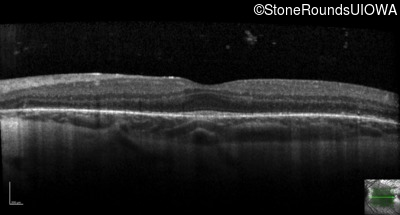

Optical Coherence Tomography - Right - 20/32

Exemplar / OCT Stack

OCT Stack